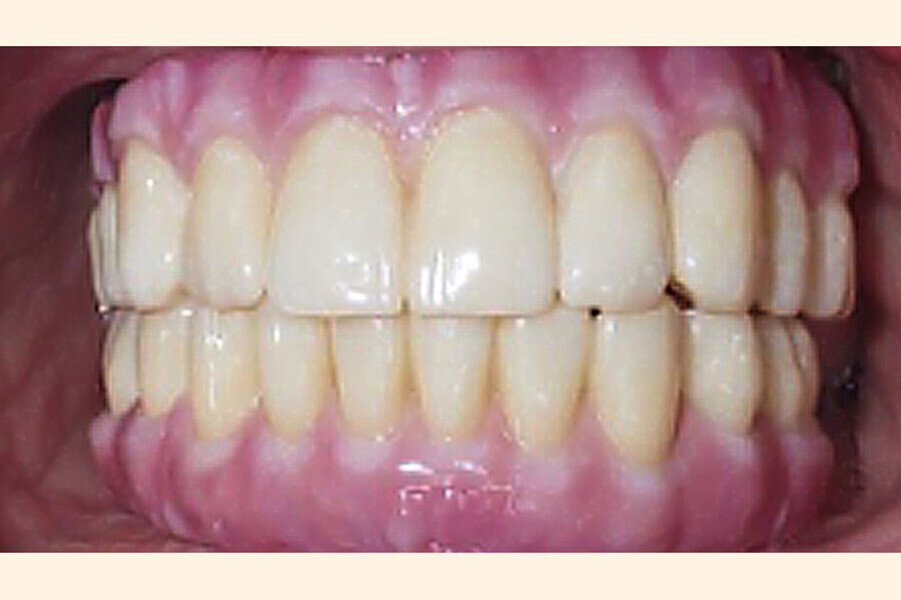

Fig. 10. Prótesis híbrida inmediata con 10 años de evolución y Rx Control a los 10 años.

Fig. 11. Prótesis híbrida inmediata con 10 años de evolución y Rx Control a los 10 años.